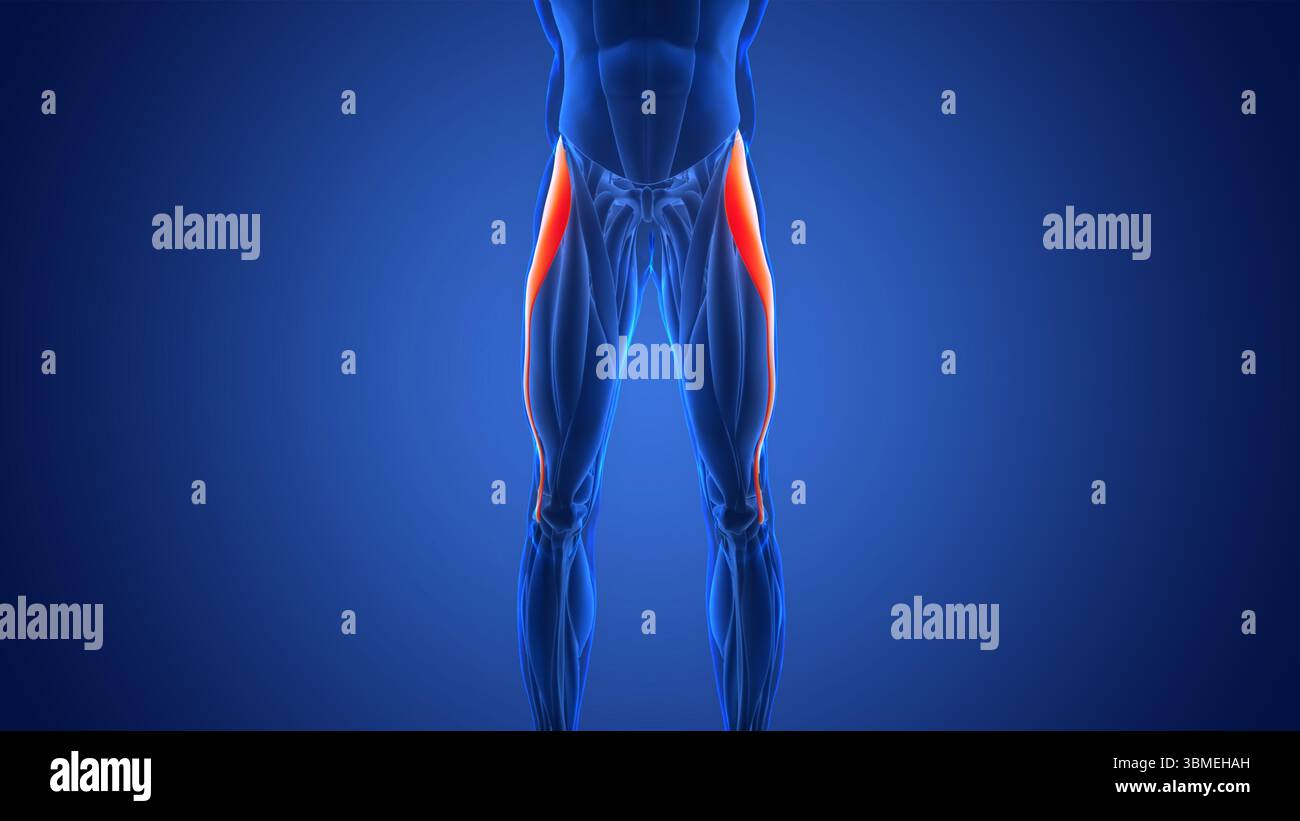

Human Muscular System Leg Muscles Tensor Fasciae Latae Muscles Anatomy Stock Photohttps://www.alamy.com/image-license-details/?v=1https://www.alamy.com/human-muscular-system-leg-muscles-tensor-fasciae-latae-muscles-anatomy-image700771049.html

Human Muscular System Leg Muscles Tensor Fasciae Latae Muscles Anatomy Stock Photohttps://www.alamy.com/image-license-details/?v=1https://www.alamy.com/human-muscular-system-leg-muscles-tensor-fasciae-latae-muscles-anatomy-image700771049.htmlRF3CM2THD–Human Muscular System Leg Muscles Tensor Fasciae Latae Muscles Anatomy

This 3d illustration shows a view of the tensor fasciae latae muscles on xray musculature Stock Photohttps://www.alamy.com/image-license-details/?v=1https://www.alamy.com/this-3d-illustration-shows-a-view-of-the-tensor-fasciae-latae-muscles-on-xray-musculature-image685304099.html

This 3d illustration shows a view of the tensor fasciae latae muscles on xray musculature Stock Photohttps://www.alamy.com/image-license-details/?v=1https://www.alamy.com/this-3d-illustration-shows-a-view-of-the-tensor-fasciae-latae-muscles-on-xray-musculature-image685304099.htmlRF3BPX8AB–This 3d illustration shows a view of the tensor fasciae latae muscles on xray musculature

Human Muscular System Leg Muscles Tensor Fasciae Latae Muscles Anatomy Stock Photohttps://www.alamy.com/image-license-details/?v=1https://www.alamy.com/human-muscular-system-leg-muscles-tensor-fasciae-latae-muscles-anatomy-image700771060.html

Human Muscular System Leg Muscles Tensor Fasciae Latae Muscles Anatomy Stock Photohttps://www.alamy.com/image-license-details/?v=1https://www.alamy.com/human-muscular-system-leg-muscles-tensor-fasciae-latae-muscles-anatomy-image700771060.htmlRF3CM2THT–Human Muscular System Leg Muscles Tensor Fasciae Latae Muscles Anatomy

This 3d illustration shows the tensor fasciae latae muscles anatomical position on xray body Stock Photohttps://www.alamy.com/image-license-details/?v=1https://www.alamy.com/this-3d-illustration-shows-the-tensor-fasciae-latae-muscles-anatomical-position-on-xray-body-image685304102.html

This 3d illustration shows the tensor fasciae latae muscles anatomical position on xray body Stock Photohttps://www.alamy.com/image-license-details/?v=1https://www.alamy.com/this-3d-illustration-shows-the-tensor-fasciae-latae-muscles-anatomical-position-on-xray-body-image685304102.htmlRF3BPX8AE–This 3d illustration shows the tensor fasciae latae muscles anatomical position on xray body

Human Muscular System Leg Muscles Tensor Fasciae Latae Muscles Anatomy Stock Photohttps://www.alamy.com/image-license-details/?v=1https://www.alamy.com/human-muscular-system-leg-muscles-tensor-fasciae-latae-muscles-anatomy-image700771059.html

Human Muscular System Leg Muscles Tensor Fasciae Latae Muscles Anatomy Stock Photohttps://www.alamy.com/image-license-details/?v=1https://www.alamy.com/human-muscular-system-leg-muscles-tensor-fasciae-latae-muscles-anatomy-image700771059.htmlRF3CM2THR–Human Muscular System Leg Muscles Tensor Fasciae Latae Muscles Anatomy

Human Muscular System Leg Muscles Tensor Fasciae Latae Muscles Anatomy Stock Photohttps://www.alamy.com/image-license-details/?v=1https://www.alamy.com/human-muscular-system-leg-muscles-tensor-fasciae-latae-muscles-anatomy-image700771054.html

Human Muscular System Leg Muscles Tensor Fasciae Latae Muscles Anatomy Stock Photohttps://www.alamy.com/image-license-details/?v=1https://www.alamy.com/human-muscular-system-leg-muscles-tensor-fasciae-latae-muscles-anatomy-image700771054.htmlRF3CM2THJ–Human Muscular System Leg Muscles Tensor Fasciae Latae Muscles Anatomy

Human Muscular System Leg Muscles Tensor Fasciae Latae Muscles Anatomy Stock Photohttps://www.alamy.com/image-license-details/?v=1https://www.alamy.com/human-muscular-system-leg-muscles-tensor-fasciae-latae-muscles-anatomy-image700771051.html

Human Muscular System Leg Muscles Tensor Fasciae Latae Muscles Anatomy Stock Photohttps://www.alamy.com/image-license-details/?v=1https://www.alamy.com/human-muscular-system-leg-muscles-tensor-fasciae-latae-muscles-anatomy-image700771051.htmlRF3CM2THF–Human Muscular System Leg Muscles Tensor Fasciae Latae Muscles Anatomy

Human Muscular System Leg Muscles Tensor Fasciae Latae Muscles Anatomy Stock Photohttps://www.alamy.com/image-license-details/?v=1https://www.alamy.com/human-muscular-system-leg-muscles-tensor-fasciae-latae-muscles-anatomy-image683818425.html

Human Muscular System Leg Muscles Tensor Fasciae Latae Muscles Anatomy Stock Photohttps://www.alamy.com/image-license-details/?v=1https://www.alamy.com/human-muscular-system-leg-muscles-tensor-fasciae-latae-muscles-anatomy-image683818425.htmlRF3BMEHAH–Human Muscular System Leg Muscles Tensor Fasciae Latae Muscles Anatomy